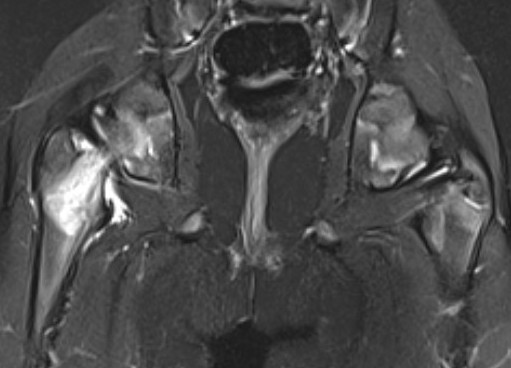

MRI

Adam et al Eur J Radiol Open 2022

- meta-analysis of MRI distinguishing between transient and septic arthitis

- bone marrow changes - 99% specific for septic arthritis

Septic arthritisSeptic arthritis

Fluid in hip joint

Hip OMHip OM

Subluxation of the hip joint with effusion and bone marrow changes

Proximal femoral osteomyelitis

Bone marrow edema and osteomyelitis in the femoral head